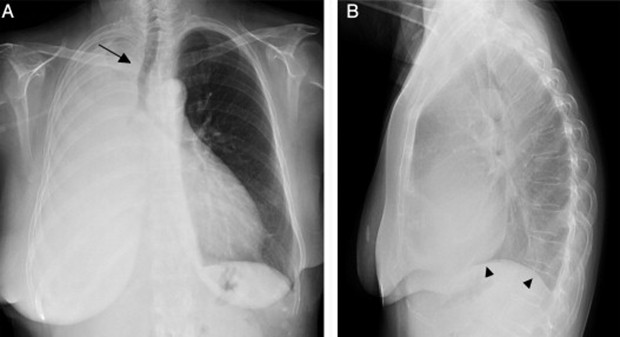

Paciente masculino de 23 años quien es llevado a consulta por productiva, malestar general fatiga y

disnea. Menciona además que últimamente ha tenido que utilizar más veces al día

su tratamiento de rescate para asma. Entre los antecedentes menciona que cree

que la Pachamama es perfecta, así que se come todas las verduras tal cual las

recoge de la siembra sin lavarla ni hervirla. Además, menciona tener malestar

abdominal, dolores tipo cólico, náuseas, meteorismo, vómitos ocasionales y

diarrea. Se le realiza un examen de heces que menciona que tiene

"huevos" y una biopsia pulmonar que verán a continuación... Con base

a toda la información... ¿Cuál de las siguientes radiografías torácicas es más

probable que tenga este paciente?

0%